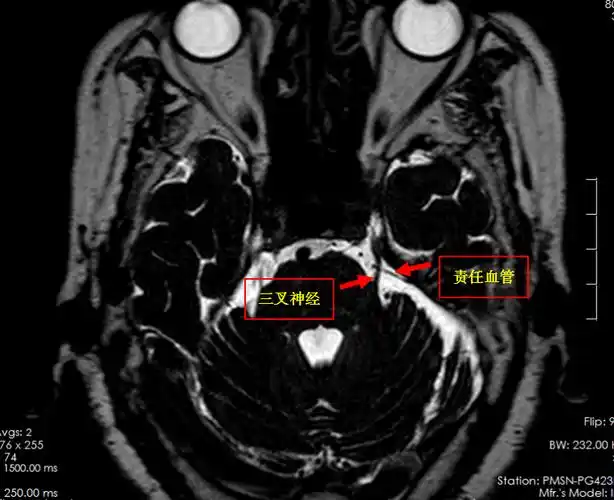

【病例-三叉神经痛】左侧面颊部疼痛4年,mvd术后疼痛消失

我院mr三叉神经薄层扫描提示:患者左侧三叉神经颅内段内侧缘小血管骑